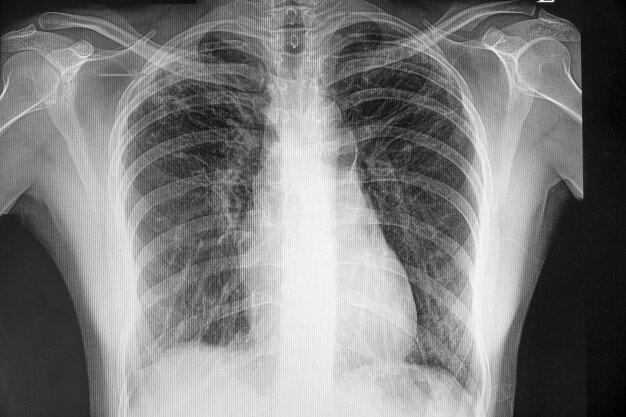

Фтизиатры предупредили о всплеске туберкулёза в конце 2020 года из-за пандемии.

В период пандемии коронавируса система борьбы с туберкулёзом остановилась. И это может привести к резкому скачку заболеваемости и смертности от него уже к концу 2020 года. Фтизиатры предупреждают, что инфекция должна жестко контролироваться, иначе заболеваемость сразу идет вверх. «Если сейчас мы не будем диагностировать туберкулез, положение дел значительно ухудшится. Даже там, где ситуация с коронавирусом напряженная, нужно уделять внимание больным туберкулезом — для этого можно использовать возможности телемедицины», – отметила спецпредставителя ВОЗ в России Мелита Вуйнович.

По данным Всемирной организации здравоохранения (ВОЗ), несмотря на определенные успехи в борьбе с туберкулёзом, смертность от этого опасного заболевания остаётся высокой. Ежегодно в мире заболевает туберкулёзом более 10 миллионов человек, десятая часть которых — дети. Смертность достигает 1,5 миллиона человек в год.

Как говорили на пресс-конференции «Уроки COVID-19: как не допустить новой эпидемии туберкулеза», Россия входит в 30 стран с самым тяжелым бременем туберкулеза — это связано и с количеством заболевших, и с показателями смертности. РФ — также одна из трех стран, на которые приходится половина всех случаев туберкулеза с множественной лекарственной устойчивостью. Поэтому в России излечивается только 55% пациентов, тогда как в Европе 70%, рассказала главный внештатный специалист-фтизиатр Минздрава, директор НМИЦ фтизиопульмонологии и инфекционных заболеваний Ирина Васильева.

Тем не менее эпидемия туберкулеза, накрывшая Россию после развала Советского Союза, постепенно шла на спад. Уровень заболеваемости ежегодно падал на 7—10%, смертности — на 12—15%. За последние шесть лет, по словам Васильевой, заболеваемость туберкулезом в России снизилась на 35%, а смертность — на 53%. Детская заболеваемость за это время снизилась в три раза.